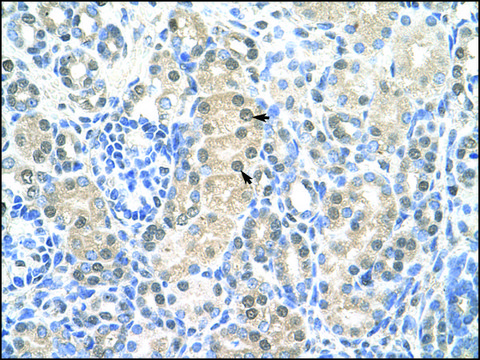

immunohistochemistry: suitable

Synthetic peptide directed towards the middle region of human MCM7

Minichromosome maintenance complex component 7 (MCM7) is one of the mini-chromosome maintenance proteins that are crucial for eukaryotic genome replication. MCM proteins are key components of the pre-replication complex, recruit replication-related proteins and form replication forks. MCM7 interacts with receptor for activated protein kinase C 1 (RACK1) and controls DNA synthesis and the entry of the cells into S phase.

MCM7 is one of the pivotal DNA replication licensing factors in controlling DNA synthesis and cell entry into S phase. Its expression and DNA copy number are some of the most predictive factors for the growth and behavior of human

The purpose of this study is to identify a better potential biomarker for the prognosis of patients with non-small cell lung cancer (NSCLC). The expressions of Nek2, MCM7, and Ki-67 were evaluated in 270 NSCLC tissues using immunohistochemical and immunofluorescence